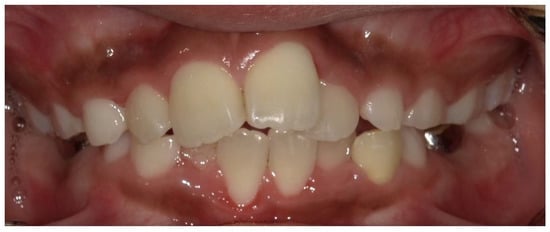

- Wato, K.; Okawa, R.; Matayoshi, S.; Ogaya, Y.; Nomura, R.; Nakano, K. X-linked hypophosphatemia diagnosed after identification of dental symptoms. Ped. Dent. J. 2020, 30, 115–119. [Google Scholar] [CrossRef]

- Okawa, R.; Hamada, M.; Takagi, M.; Matayoshi, S.; Nakano, K. A Case of X-Linked Hypophosphatemic Rickets with Dentin Dysplasia in Mandibular Third Molars. Children 2022, 9, 1304. [Google Scholar] [CrossRef]